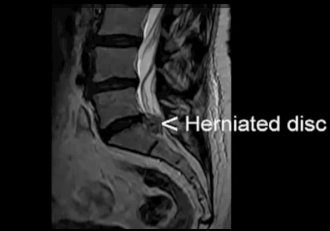

Однако в результате дегенеративного заболевания дисков (остеохондроза) (гиперссылка на страницу остеохондроз) происходит замещение волокон фиброзного кольца на рубцовую ткань.

Волокна рубцовой ткани не обладают такой прочностью и эластичностью как волокна фиброзного кольца.

Это ведет к ослаблению диска и при повышении внутридискового давления может приводить к разрыву фиброзного кольца.